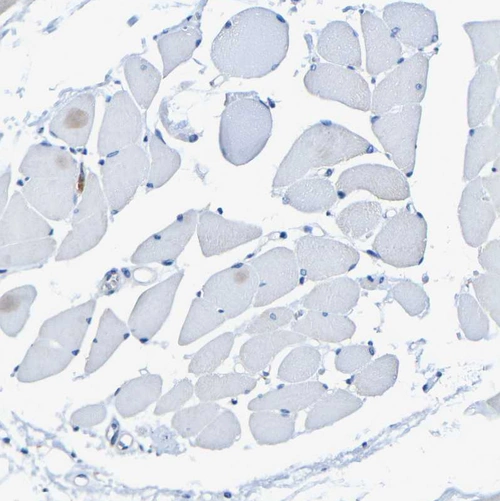

Immunohistochemistry analysis in human cerebral cortex and skeletal muscle tissues using HPA013796 antibody. Corresponding P2RY12 RNA-seq data are presented for the same tissues.